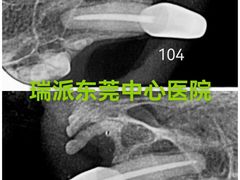

瑞派24小时宠物医院·转诊中心·异宠 | 25-08-01

报错